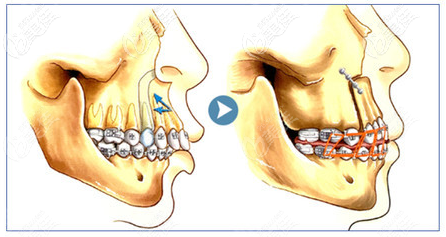

上顎骨突出矯正手術(shù)屬于四級頜面整形手術(shù),具有一定的風(fēng)險,為了降低手術(shù)風(fēng)險,建議選大型正規(guī)具備四級頜面磨骨資質(zhì)的醫(yī)院和醫(yī)生進(jìn)行手術(shù)。

我原來也是上顎骨突出,自卑了很長很長時間,考慮了很久去做了矯正手術(shù),前前后后做上顎骨突出矯正手術(shù)花了6萬多元吧。臉型改善還是很明顯的,臉型好看了,五官跟著都變美了。

上顎骨突出矯正手術(shù)肯定是有風(fēng)險的,所以我找的北京非常有名的磨骨醫(yī)生給我做的手術(shù)。建議你也一定要選擇正規(guī)有資質(zhì)的醫(yī)院做手術(shù)。